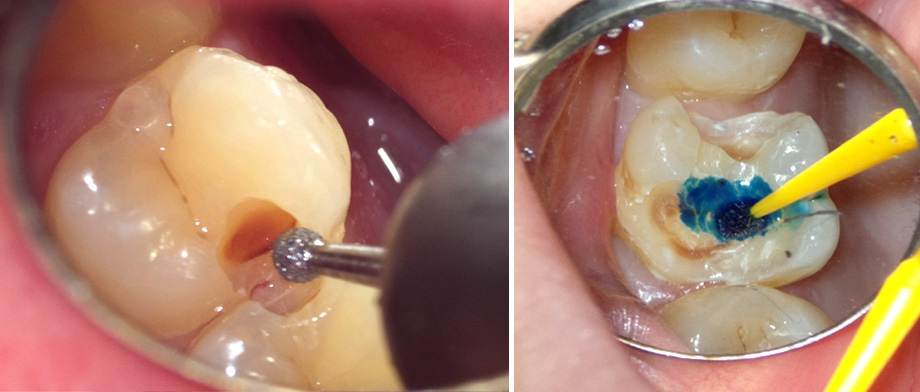

むし歯除去

マイクロスコープ、う蝕検知液を使用して、むし歯を過不足なく除去します